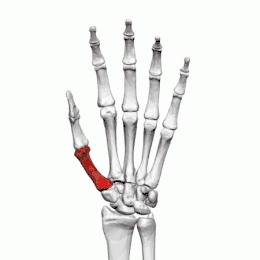

Aspect clinique

Fractures

Les fractures des os métacarpiens représentent 30 à 40 % de toutes les fractures de la main, dont 25 % surviennent dans le premier métacarpien (deuxième après les fractures du cinquième métacarpien) et 80% des fractures du premier métacarpien surviennent à sa base[2].

Les fractures courantes du premier métacarpien sont la fracture de Bennett et la fracture de Rolando.

La fracture des quatrième et cinquième métacarpien est fréquente après un coup de poing : fracture du boxeur.

Fracture du 5e métacarpe, également dénommée « fracture du boxeur »